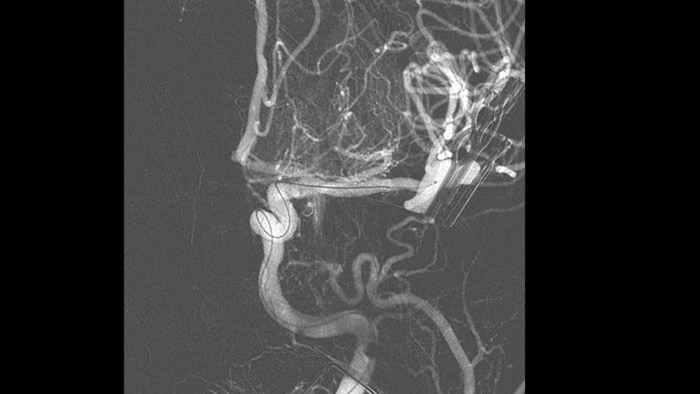

SmartCT Vasoを使用すると、血管内ステント、フローダイバータ、その他のデバイスの視認性が向上するだけでなく、血管の形態を穿通枝レベルまで詳細に確認できます。この画像取得技術は、コーンビームCTスキャンと動脈内造影注入に基づいています。この手法はフローダイバータ、その他のデバイスの視認性が向上するだけでなく、血管の形態を穿通枝レベルまで詳細に確認できます。この画像取得技術は、コーンビームCTスキャンと動脈内造影注入に基づいています。この手法はフローダイバータステントで治療した動脈瘤の追跡検査に使用されるケースが増えています。

SmartCT Angioでは、数秒で3D再構成でき、動脈瘤と血管との位置関係、形状、サイズ、重症度を評価し、治療のためのターゲットアングルの決定を支援します。3D画像は高い空間分解能と患者の体動を自動補正して再構成表示します。